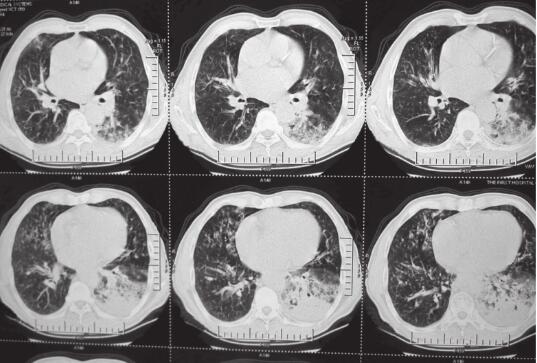

患者,刘某,男,66岁。因“反复咳嗽、咳痰2年余,再发加重3天”于2014年3月7日入院。自2012年以来,患者无明显诱因出现反复咳嗽、咳痰,多为白色泡沫痰,咳嗽剧烈时伴胸闷、气喘不适,间断高热,多次在外院住院治疗,每经抗感染及止咳祛痰等对症治疗后病情可缓解,出院后患者咳嗽、咳痰症状仍反复。自2012年起病以来,患者多次行肺部CT(图1~图4)检查提示“左下肺大片状及右上叶片状阴影”,行抗感染治疗后右肺上叶稍吸收,左下肺片状影吸收欠佳。2013年8月考虑患者“肺结核”不能排除,在本市结核病医院,查T-spot(+),后给予三联抗结核(异烟肼+利福平+乙胺丁醇)治疗2个月,咳嗽、咳痰未见明显好转。2013年11月曾因咳嗽、咳痰加重入我科,给予抗感染(左氧氟沙星)及继续抗结核(异烟肼+利福平+乙胺丁醇)治疗,期间患者因大便潜血(+)行肠镜检查,提示“乙状结肠直肠新生物”,病理检查示“乙状结肠腺癌”,于2013年12月8日转普外科行“乙状结肠癌根治术”。此次入院前3天,患者受凉后再发咳嗽,咳白色泡沫痰,量较多,偶为粉红色泡沫痰,咳嗽剧烈时感憋气、胸痛,无畏寒、发热,无恶心、呕吐,无双下肢水肿等不适。

图1 2013年1月7日右上肺(A)及左下肺(B)

图2 2013年8月27日肺部CT

图3 2013年10月21日肺部CT